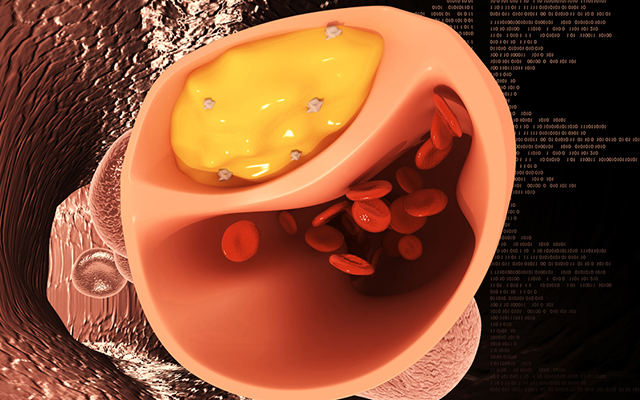

뇌경색은 뇌의 혈관이 막혀서 뇌에 산소와 영양분이 공급되지 않게 되는 상태를 의미합니다. 이런 혈액 공급이 차단되면 뇌세포가 손상되거나 사멸하게 됩니다. 급성 뇌경색은 시간이 지남에 따라 위험성이 증가하므로, 초기 증상을 빠르게 인식하는 것이 필요합니다. 뇌경색은 주로 고혈압, 고지혈증, 당뇨병 등의 만성 질환과 연관이 있습니다.

이 질환의 발생 원인은 다양합니다. 동맥경화증, 심장병, 과호흡증 등이 주요한 원인으로 작용할 수 있습니다. 무엇보다도 뇌경색을 예방하려면 평소에 건강한 식습관과 규칙적인 운동을 유지하는 것이 중요합니다. 그럼 이제 뇌경색의 초기 증상에 대해 알아보도록 하겠습니다.